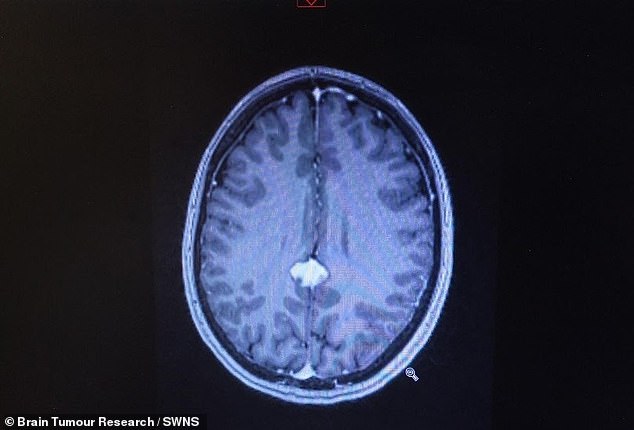

Doctors diagnosed her with a posterior falcine meningioma¿a low-grade tumour in a location too dangerous for surgery. April's brain scan is pictured above, the tumour showing in white

Doctors diagnosed her with a posterior falcine meningioma—a low-grade tumour in a location too dangerous for surgery. April’s brain scan is pictured above, the tumour showing in white

A scan at her local hospital revealed a mass deep in the centre of her brain.

Doctors diagnosed her with a posterior falcine meningioma—a low-grade tumour in a location too dangerous for surgery.